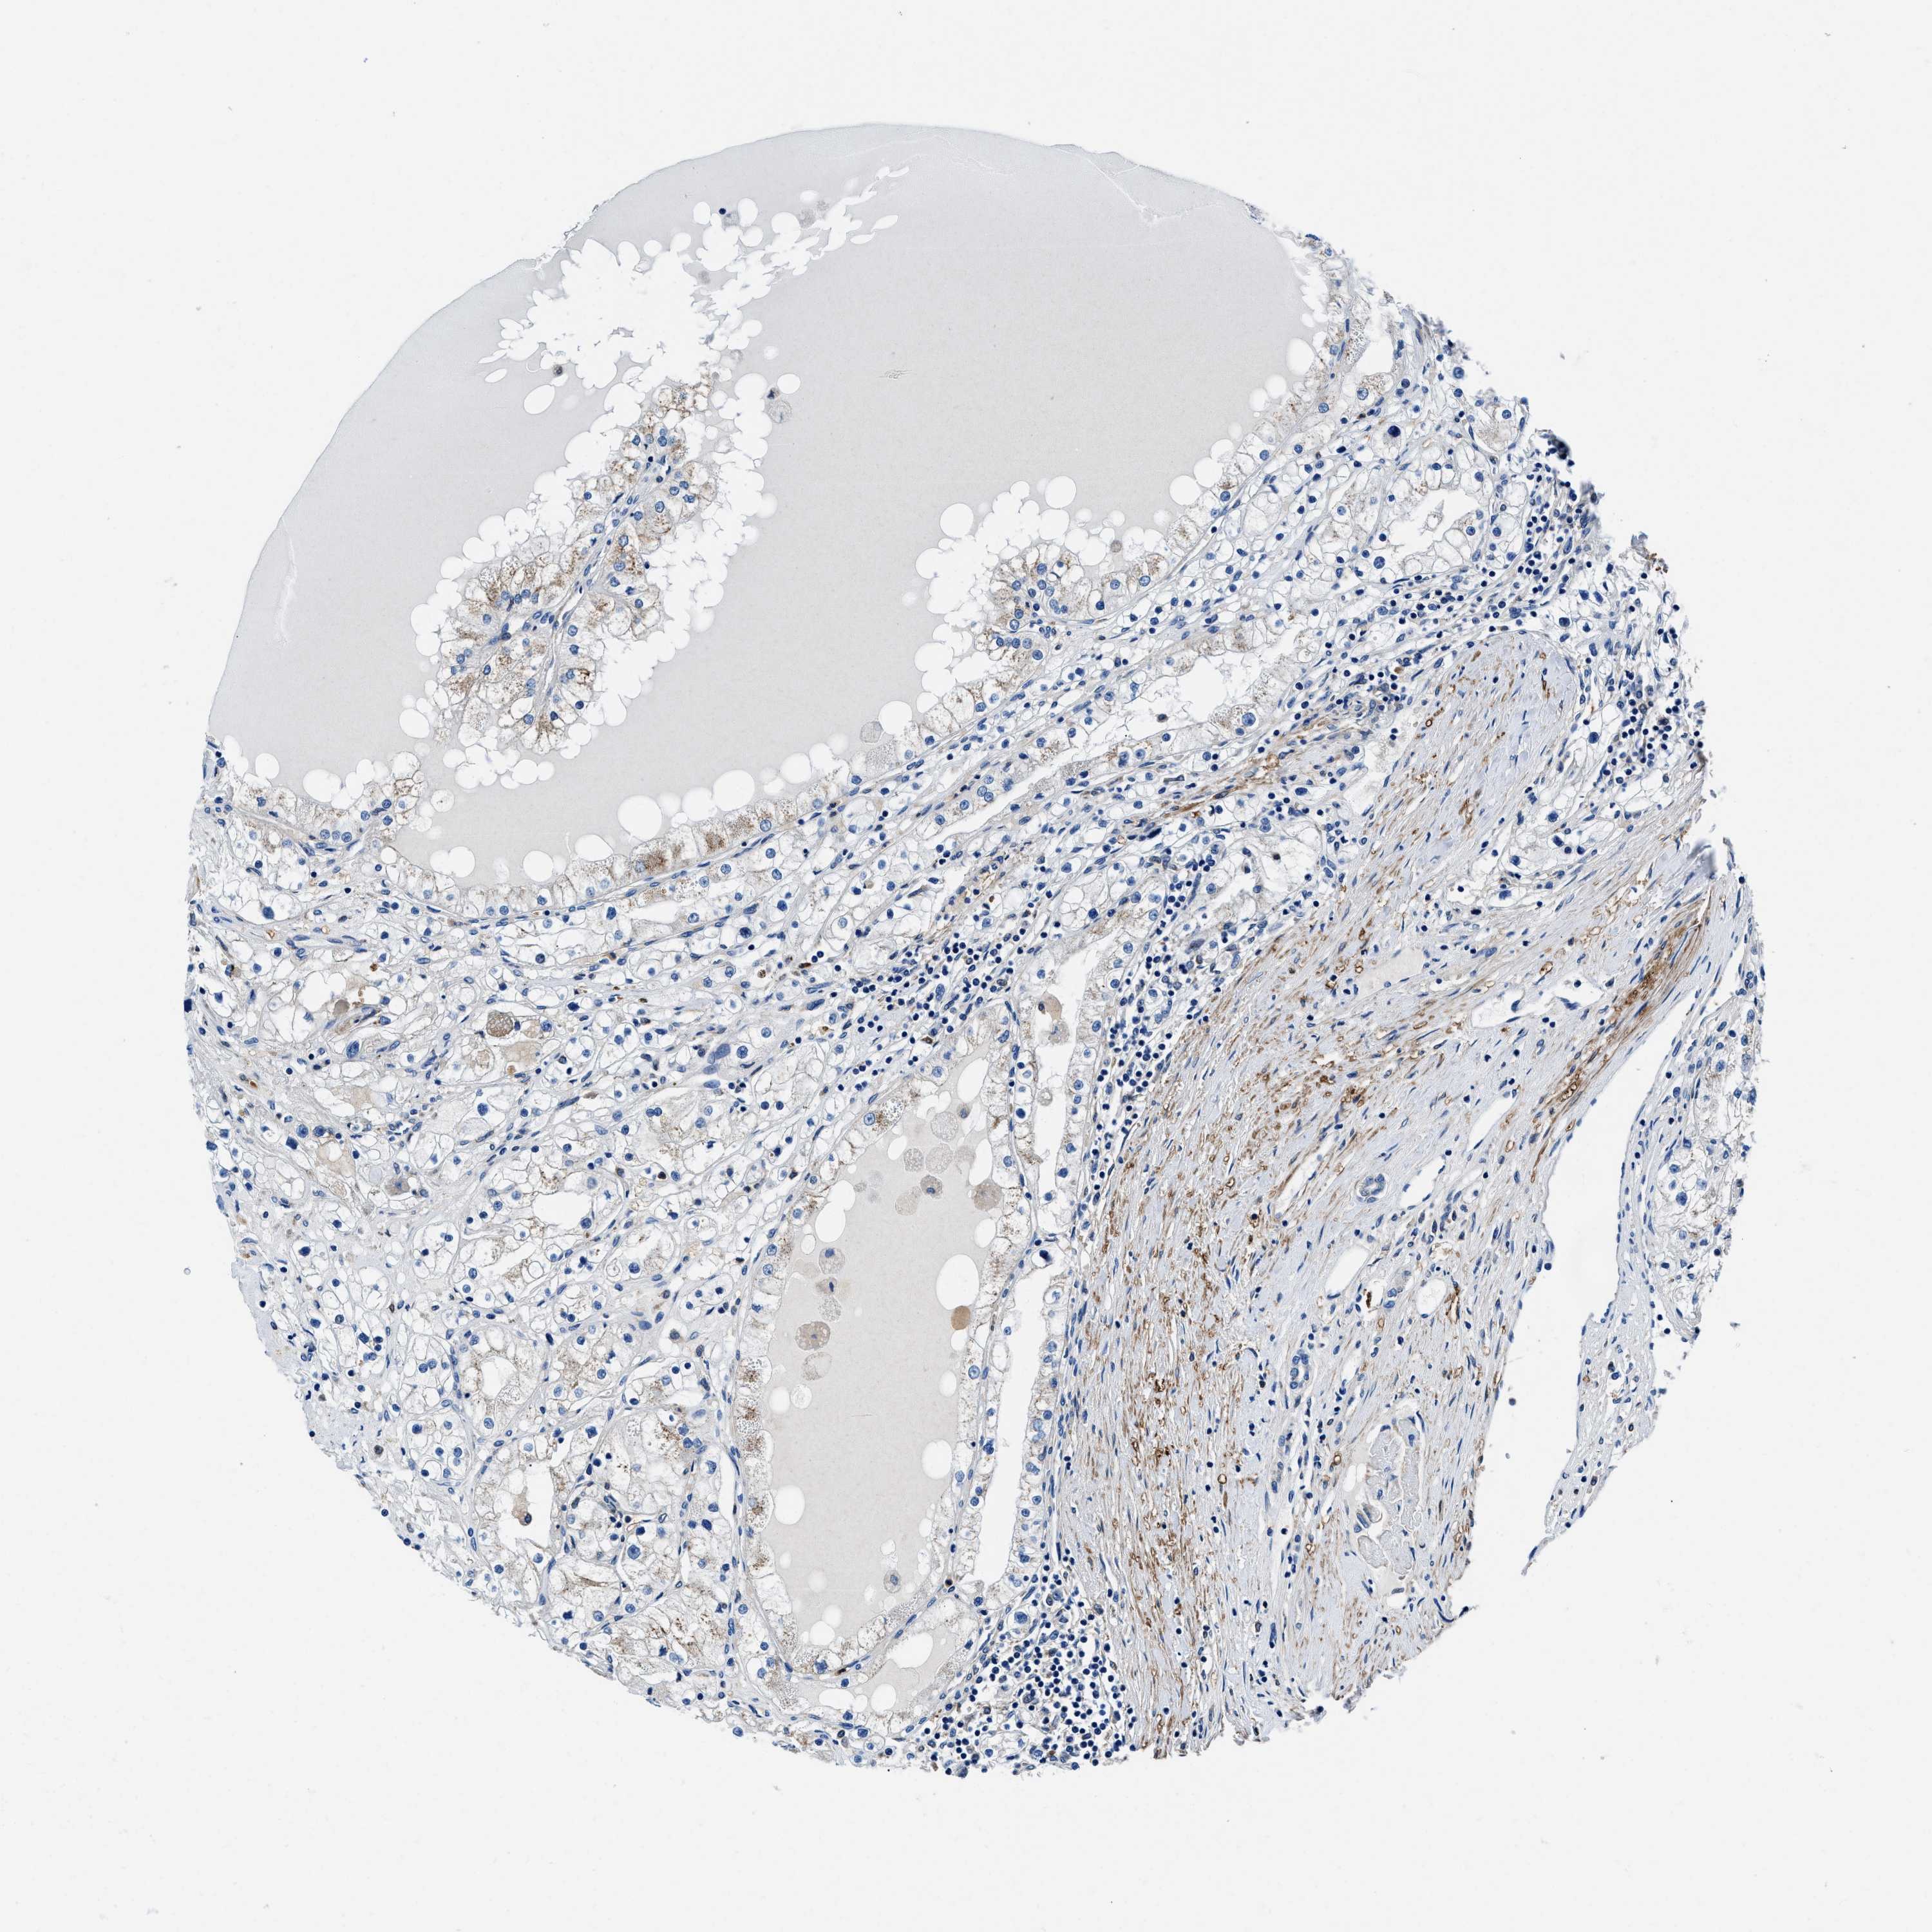

TCGA RNA samplesi

RNA-seq data is reported as average FPKM (number Fragments Per Kilobase of exon per Million reads), generated by the The Cancer Genome Atlas (TCGA) .

Normal distribution across the dataset is visualized with box plots, shown as median and 25th and 75th percentiles. Points are displayed as outliers if they are above or below 1.5 times the interquartile range. FPKM values of the individual samples are presented next to the box plot.

Average pTPM 1.4

Number of samples 100